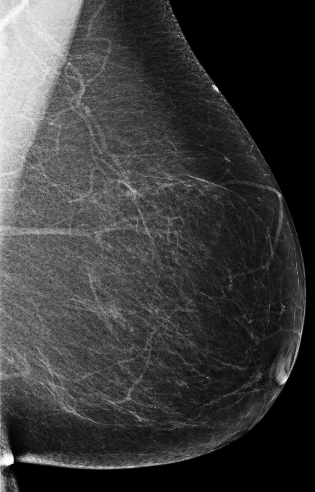

Masking refers to the phenomenon in which a tumor is hidden by the surrounding breast tissue, causing the cancer to be difficult or even impossible to discern with regular mammography, as seen in Figure 2. Masking can also result in large invasive cancers111We define large invasive cancers as those confirmed to have spread and be 2cm at time of diagnosis. – a small cancer may be difficult to discern in certain images, allowing it to grow to a more lethal size. Masking is correlated with breast density, as it has been shown that cancer in dense breasts is more likely to be missed during screening [5, 6, 7]. Density can be subjectively assessed by radiologists via the BI-RADS density standard (ACR) [8, 9], or measured by automated tools such as Libra [10]. These density measurements, however, do not perfectly correlate with masking potential. Radiologists consider the distribution and pattern of tissue when assessing masking potential, and have called for automated methods to assess the masking effect [11]. Until now, the question of exactly how masking potential should be quantified remains an open one, although some subjective notion has been added to certain categories of the most recent edition of BI-RADS density [12].

CSAW-M consists of screening mammograms along with metadata describing expert masking potential assessments, clinical endpoints, density measures, and image acquisition parameters. CSAW-M is part of an ecosystem of mammography datasets based on the CSAW population-based cohort [25], depicted in Figure 2. CSAW is a collection of millions of screening mammograms of screening participants aged 40 to 74 gathered from the three breast centers of the Stockholm region between 2008 and 2015. The CSAW case-control dataset, hereafter referred to as CSAW for brevity, is a subset of the full CSAW cohort containing all cancers, along with a random sampling of healthy screens from the Karolinska breast center. A portion of CSAW (2,580 screening participants) is designated as a private held-out test set, unavailable to the public, for controlled benchmarking of various tasks. CSAW-M is subset of CSAW, created here, to study masking. It is divided into a training set (9,523 examples), a public test set (497 examples), and a private test set corresponding to those in CSAW (475 examples). A summary of the dataset is provided in Table 2. CSAW-M partially overlaps with CSAW-S, a sister dataset focused on segmentation in mammograms [24]. Below, we describe the procedure followed to create CSAW-M depicted in Figure 3.

Screening participants from CSAW were selected for inclusion to CSAW-M according to a flowchart found in Appendix A. As shown in Figure 3, starting from the CSAW population, we selected participants with mammographic screening exams from Karolinska University Hospital acquired with Hologic devices after the data was curated. From these sets of participants, we selected images as follows: the most recent mediolateral oblique (MLO) view of the breast was included, since MLO offers the best visualization of the breast [26]. If a selected participant had cancer, we selected the image of the contralateral breast (the one without cancer) to avoid contaminating the masking potential annotation task with actual tumors. Otherwise, the image was chosen with a random breast side. This resulted in screening participants fitting our selection criteria. To form our private test set, we finally sampled from the participants who correspond to the private split. From the participants belonging to the public split, we included all with cancer and sampled from the healthy population (as described below) to form our public data.